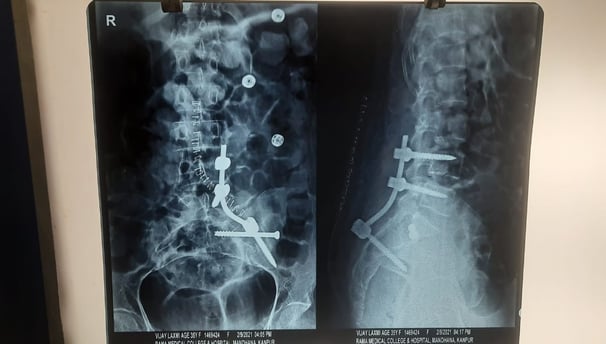

Renowned orthopedic surgeon in Kanpur, dedicated to providing exceptional care in joint replacement, fracture treatment, sports injuries, and spine care. Your health is our priority.

Expert orthopedic treatments for joint replacement, sports injuries, fractures, and spine care in Kanpur.